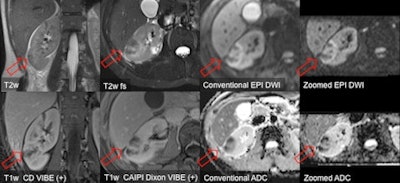

One of the modified sequences that benefits from two independent transmit channels is known as the zoomed technique, which reduces the field-of-view to save phase-encoding steps and thus imaging time. It is already routinely implemented for the abdomen in Mannheim in combination with diffusion-weighted imaging (DWI) based on single-shot, spin-echo echo-planar imaging (EPI). With zoomed EPI-DWI, it is possible to reduce the field-of-view without ghosting artifacts and with vastly reduced distortion artifacts.

Zoomed EPI-DWI using pTX MRI can allow clearer visualization of transitional cell carcinoma and renal abscess. Images courtesy of Dr. Stefan Haneder.

"In the pancreas, intraductal papillary mucinous neoplasms (IPMNs) can be visualized as small cystic lesions. One criterion for the likelihood of malignancy is the presence of intramural nodules. With zoomed EPI-DWI, visualization and even ADC value assessment of small lesions within the cysts is possible," he said.